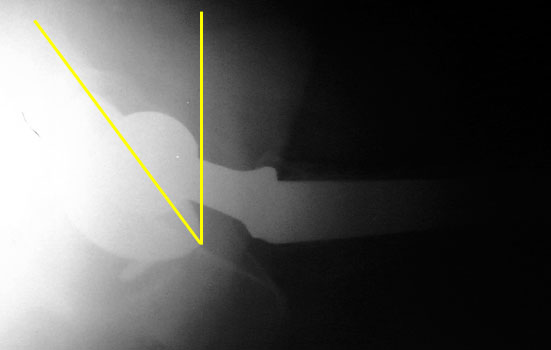

Femoral neck anteversion is difficult to accurately evaluate on radiographs, and can only be qualitatively assessed on a groin lateral view. This view is difficult to obtain, especially in the elderly or post operative patient, and is effected by pelvic or thigh rotation.

CT is the imaging modality of choice to evaluate for femoral neck anteversion.

Femoral neck anteversion on groin lateral film.